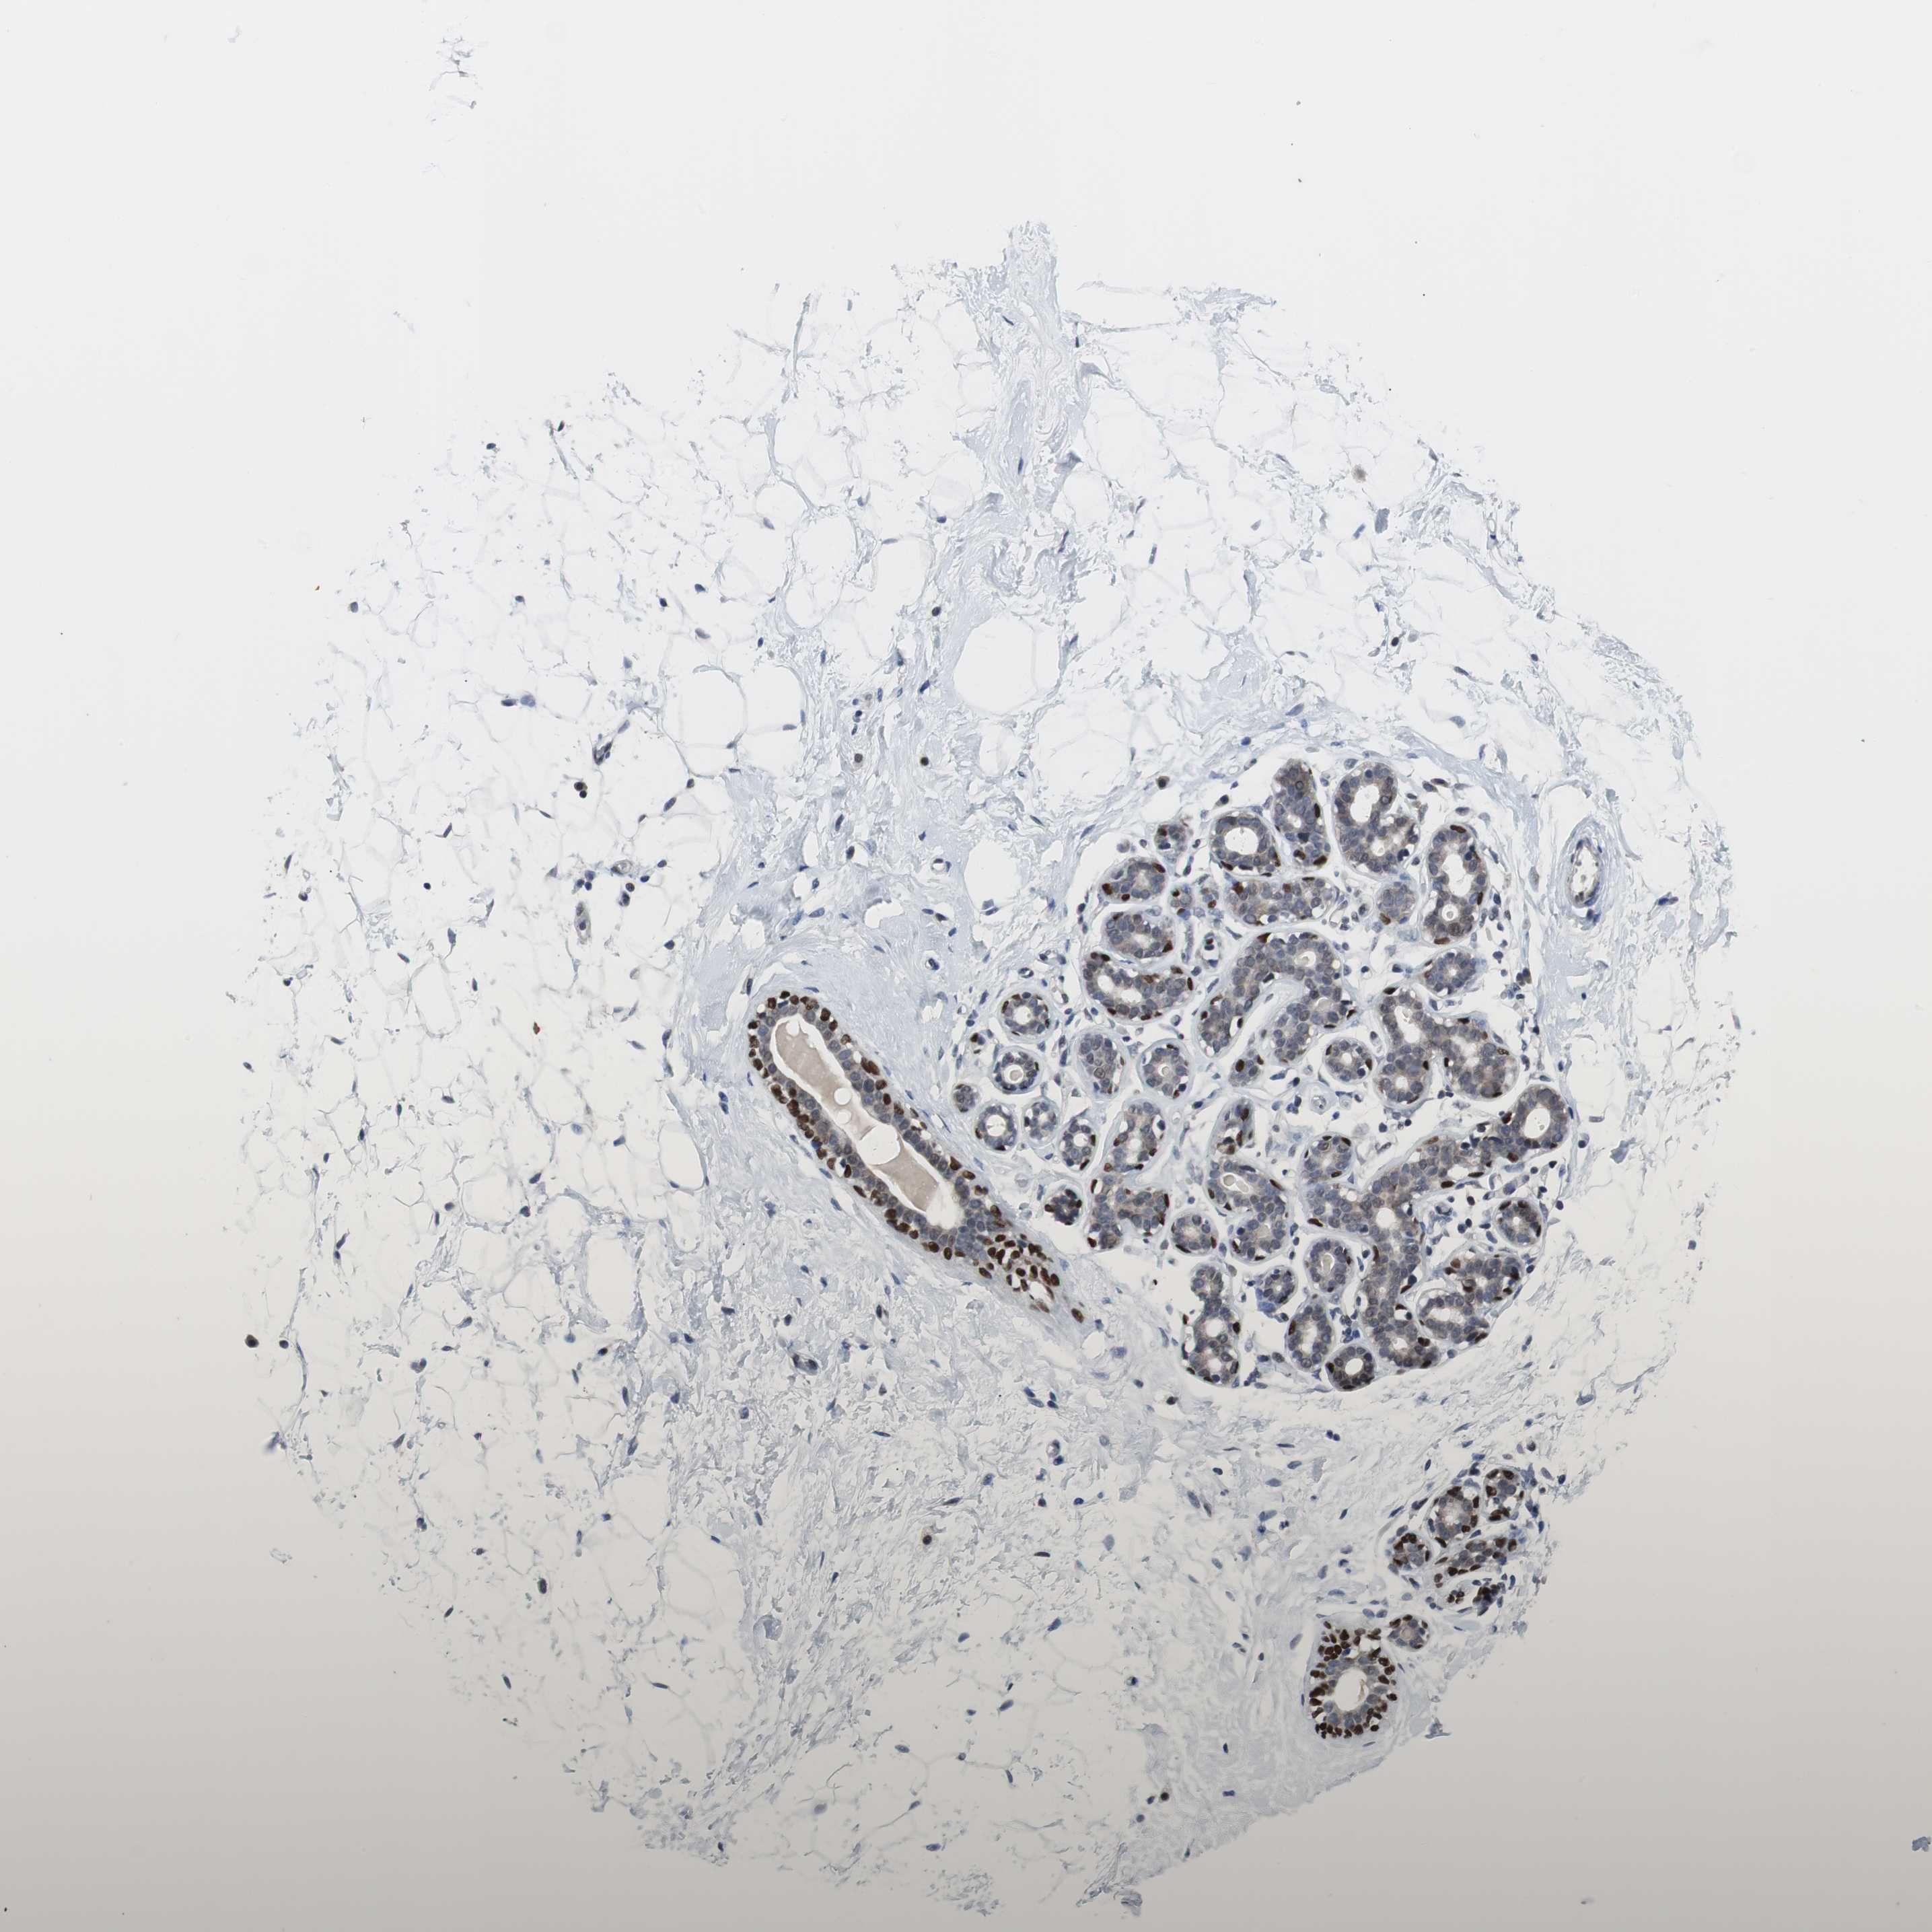

BREAST - Antibody stainingi

Antibody staining in the annotated cell types in the current human tissue is reported as not detected, low, medium, or high, based on conventional immunohistochemistry profiling in selected tissues. This score is based on the combination of the staining intensity and fraction of stained cells.

Each image is clickable and will lead to virtual microscopy that enables deeper exploration of all samples and also displays staining intensity scores, fraction scores and subcellular localization as well as patient and tissue information for each sample.

Antibody HPA006288Antibody HPA007010Antibody CAB000083

Adipocytes Not detectedLow-

Glandular cells Not detectedHighNot detected

Myoepithelial cells HighLowHigh